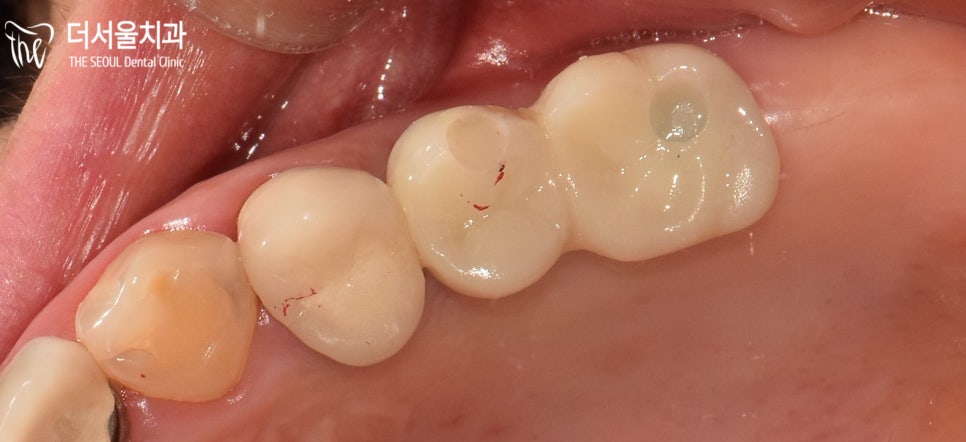

지르코니아를 사용하여 제작한

크라운을 올려드리며 마무리를 도와드렸습니다.

방끗 웃으며 너무 편안하다고 말씀해 주셨던 환자분ㅎㅎ

앞으로 맛있는 음식 편하게 드시면서 생활하셨으면 좋겠습니다.